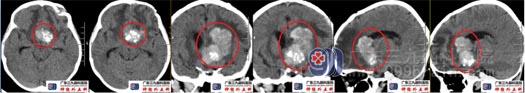

术前头颅CT鞍内示斑片状低密度影,边缘示斑点状钙化;鞍上区-左侧额叶-左侧脑室前角示一团片状高密度影,累及胼胝体,其内示多发斑片状钙化,大小约41mm×24mm×51mm,周围双侧额叶示斑片状低密度水肿影。脑室系统轻度扩大,左侧脑室受压变窄,双侧脑室后角示斑片状高密度影。头颅CTA检查:鞍内术区团块状占位性病变内血供丰富,存在多发细小血管影及钙化影,累及邻近双侧大脑前动脉A1段、A2段以上及其分支细小、狭窄,大部分显示不清;双侧大脑中后动脉存在代偿增粗延长。